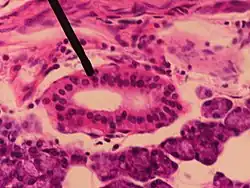

Outline of side of face, showing chief surface markings. - Microscopic slide of a human interlobular duct.

- Microscopic slide of a human striated duct.